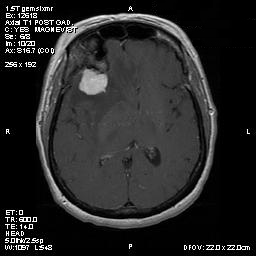

T1-weighed MR images demonstrate an extraaxial, dural based mass involving the right supraorbital region  (Panel A and B). The mass shows homogeneous enhancement  (Panel C). CT scan demonstrates as well as rim calcification (Panel E). On T2-weighed imagers, significant vasogenic edema is demonstrated despite the small size of the lesion and the extraaxial location (Panel D).